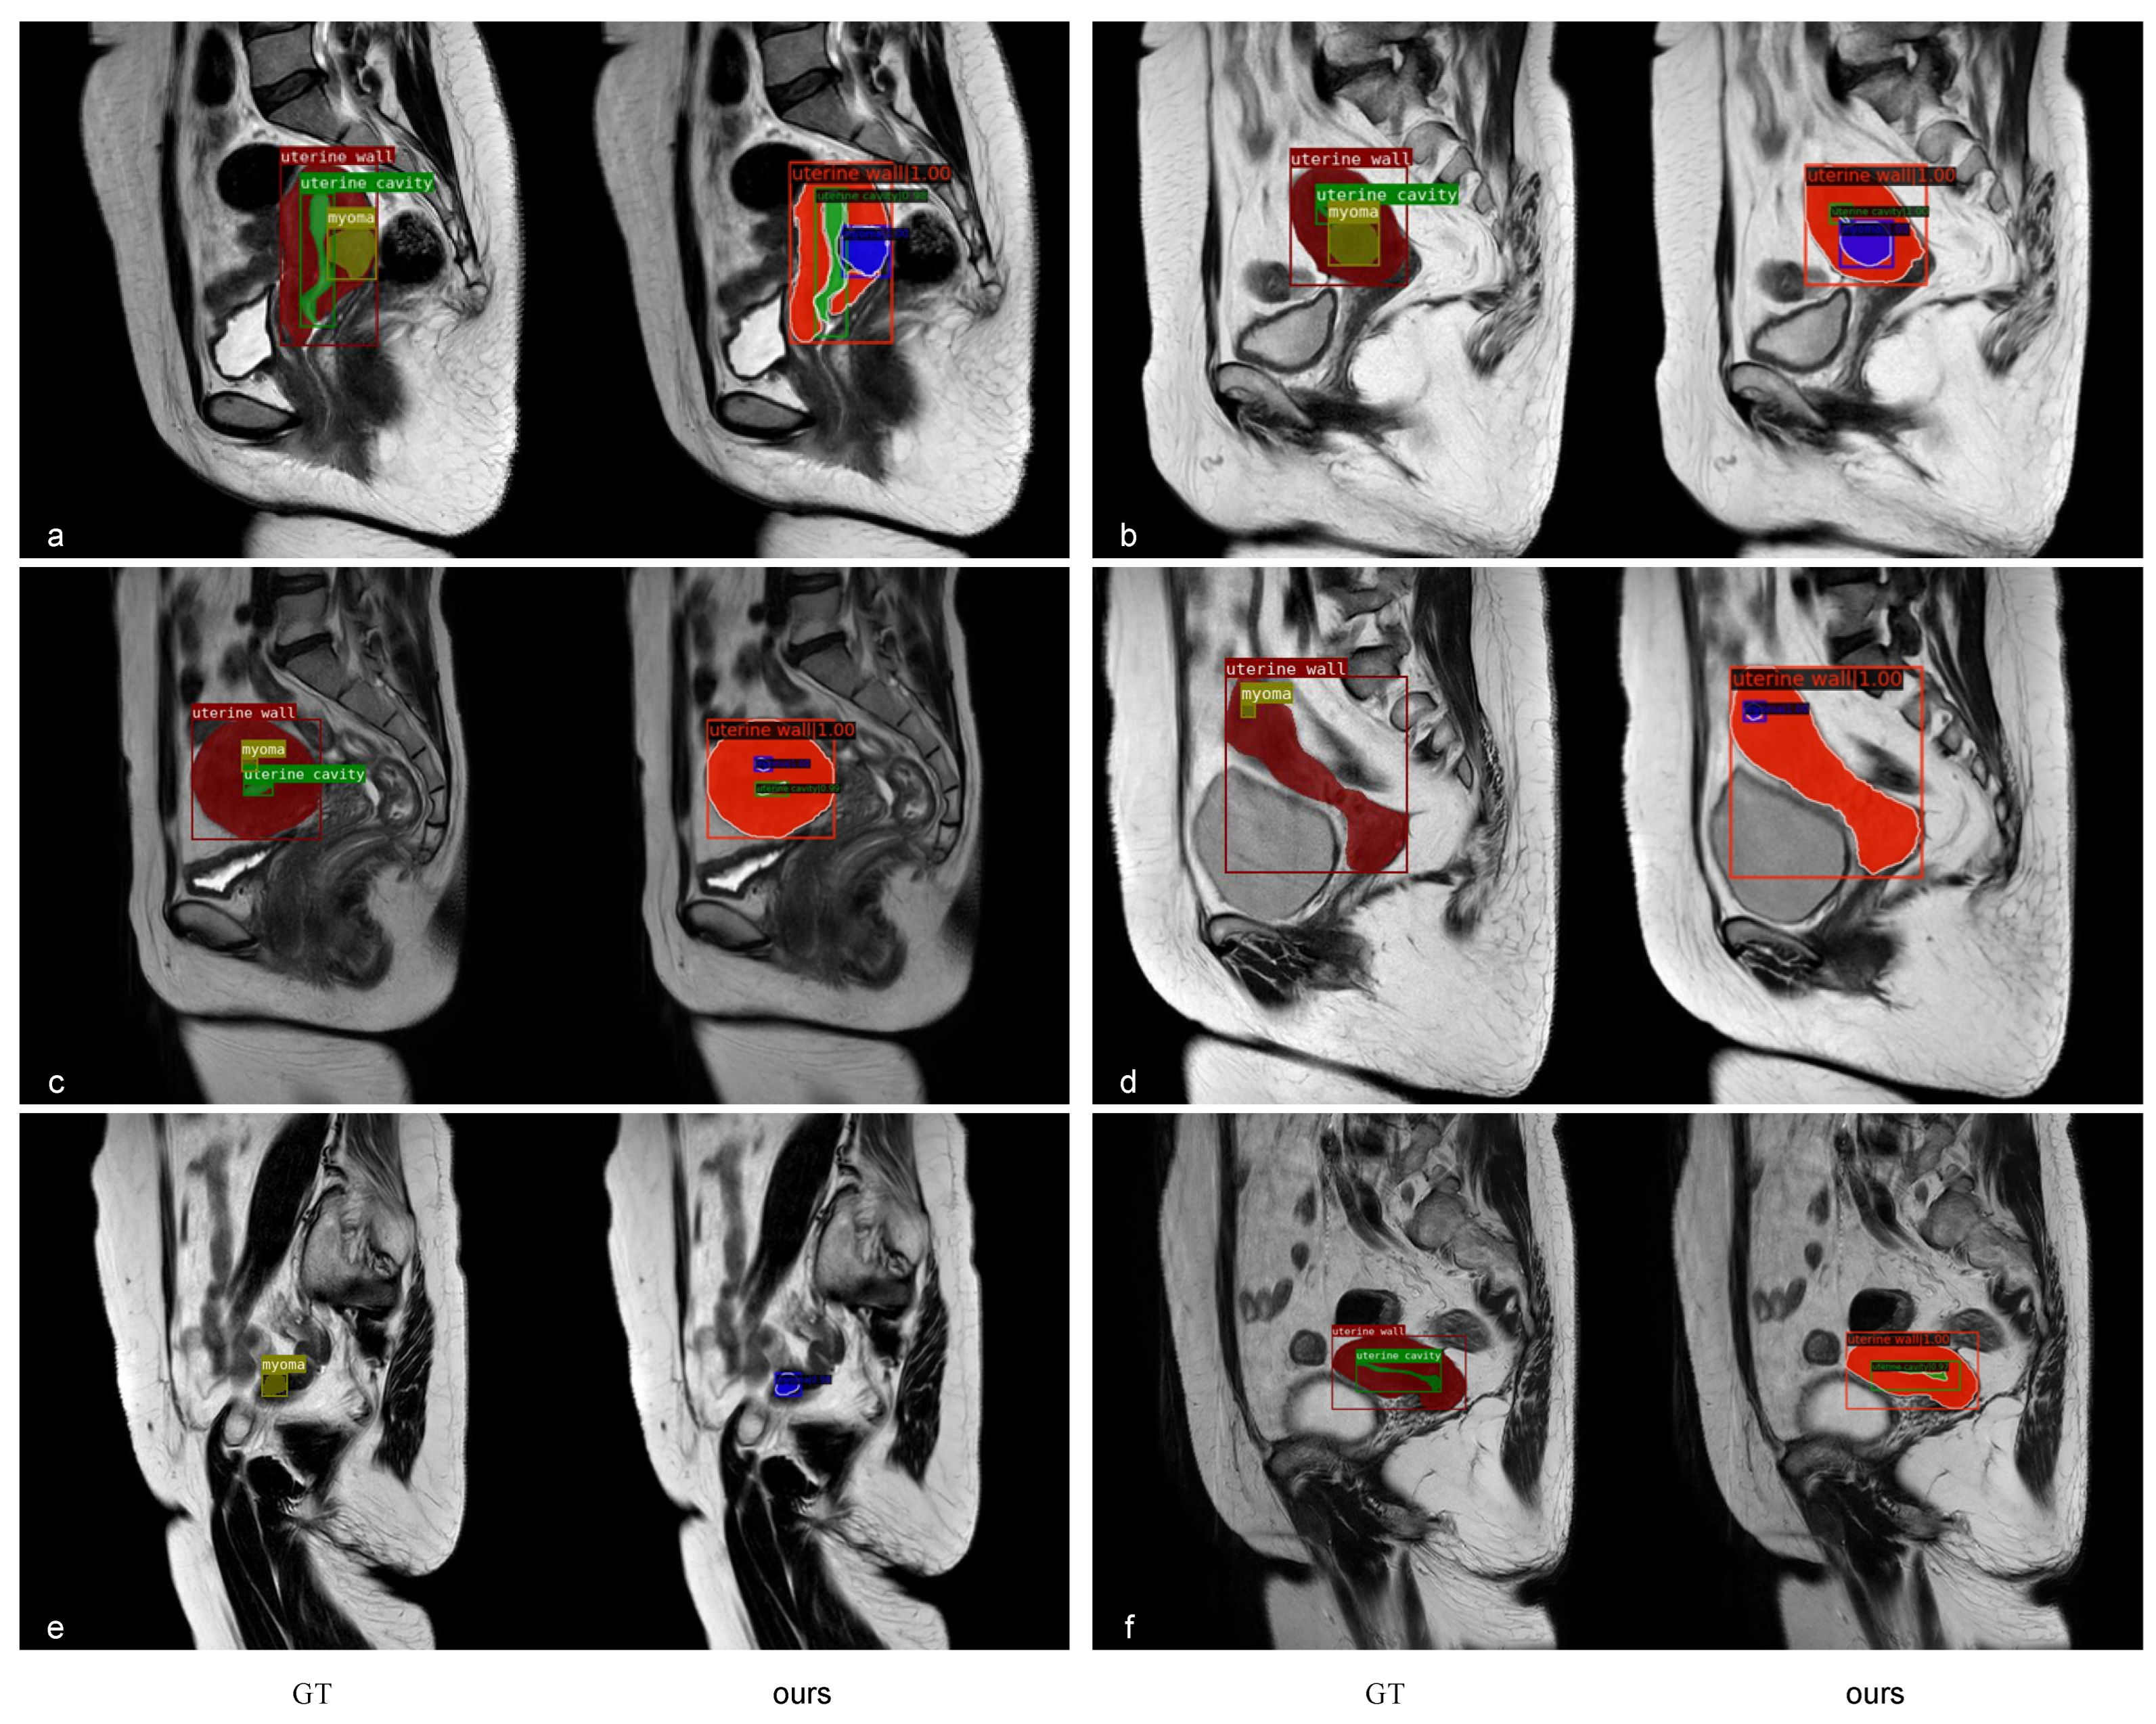

- We validated our approach with some excellent models and visualized its segmentation performance.

3.4. Comparison with Popular Models

4. Discussion